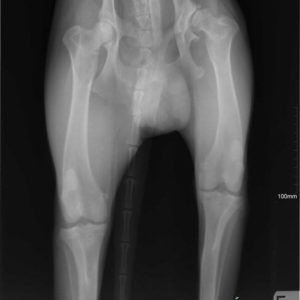

Vielen Dank an Alexander Englert, dass er möglich gemacht hat für Mex , seine Hüft- Dysplasie – Operation zu finanzieren. 🙂 Noch zweieinhalb Monate Rehabilitation und wir können eine neue Familie suchen für Mex! 🙂 Kategorie: NewsVon Csillag Alexandra2017-09-14 Share this post Share on FacebookShare on Facebook Share on XShare on X Autor: Csillag Alexandra http://www.ebarvahaz.hu KommentarnavigationZurückVorheriger Beitrag:Lola – Eine kleine wunder!NächstesNächster Beitrag:Vielen Dank Mirabella Hesz für die Spenden!Related postsTamara und ihre 7 kleinen Babys2026-01-13Hallo Mangó!2026-01-09Hallo unsere Lieben!2026-01-08Unsere neuesten Bewohner sind angekommen!2025-07-11Bözse <32025-04-10Überraschung2025-01-29